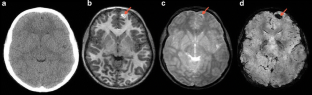

Fig. 1